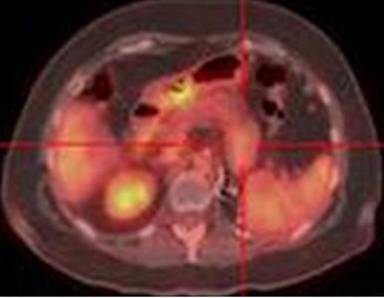

Pancreatic cancer uses TNM system, which stands for tumor (T), nodal involvement (N), and metastases (M), for staging. Stage I disease is confined to the pancreas. Stage II is extended outside the pancreas. Stage III is involved with lymph nodes. Stage IV is characterized by distant metastases. PET is more accurate than CT for M staging because it allows better detection of distant metastasis (Figure 1) and provides greater ability of differentiating benign from malignant behavior of equivocal lesions on CT. Approximately 1/3 of small metastases (<1 cm) in the liver and peritoneum were missed by CT and MRI. A meta-analysis showed that PET/CT had the highest pooled sensitivity (91%) in detecting peritoneal metastases when compared to CT and MRI [2]. PET/CT has an accuracy of 91% for primary pancreatic lesions, 85% for loco-regional staging, and 92% for restaging of pancreatic cancer [3]. PET/CT changes care management of patients (36-41% of cases) by providing a more accurate staging of pancreatic cancer [1].

|

Figure 1. a. Coronal PET maximum intensity projection image detects a distant left supraclavicular nodal metastasis (crosshair) of pancreatic cancer (arrow). b. Fused axial PET/CT image shows the corresponding left supraclavicular node (arrow). PET/CT provides an accurate M staging that is not obtainable with other conventional cross-sectional imaging modalities. |